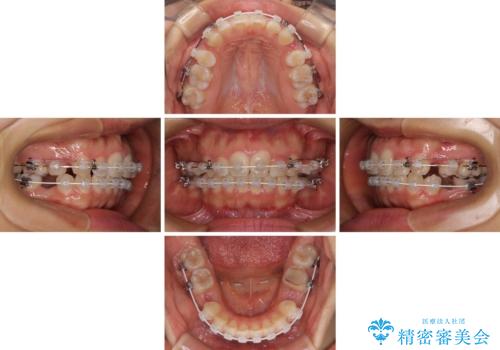

【モニター】閉じにくい口元 ワイヤー装置での抜歯矯正

- 20代女性

- 審美装置

- 2年2ヶ月

- 咬み合わせと口元の突出感を気にして来院された患者様です。

上顎に対して、下顎が後方にある咬み合わせであるため、上顎左右小臼歯のみの抜歯か、下顎左右小臼歯も抜歯とするのか悩むところでした。

まずは上顎のみ抜歯を行って矯正治療を進め、下顎小臼歯も抜歯が必要となれば速やかに抜歯することとしました。

上顎抜歯のみでは奥歯の咬み合わせを改善することが困難であったため、途中で下顎小臼歯も抜歯をしました。

抜歯のタイミングが遅れると治療期間が長期化するため、速やかに抜歯の判断をし、2年強の期間で治療を終えることができました。